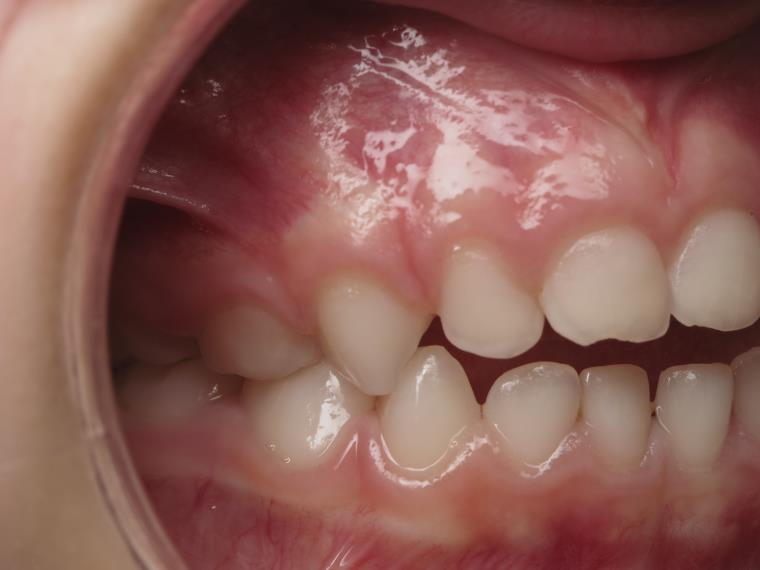

14 béance inversé gauche 5 ans

inversion postérieur coté droit et espace entre l'arcade du haut et du bas (béance)